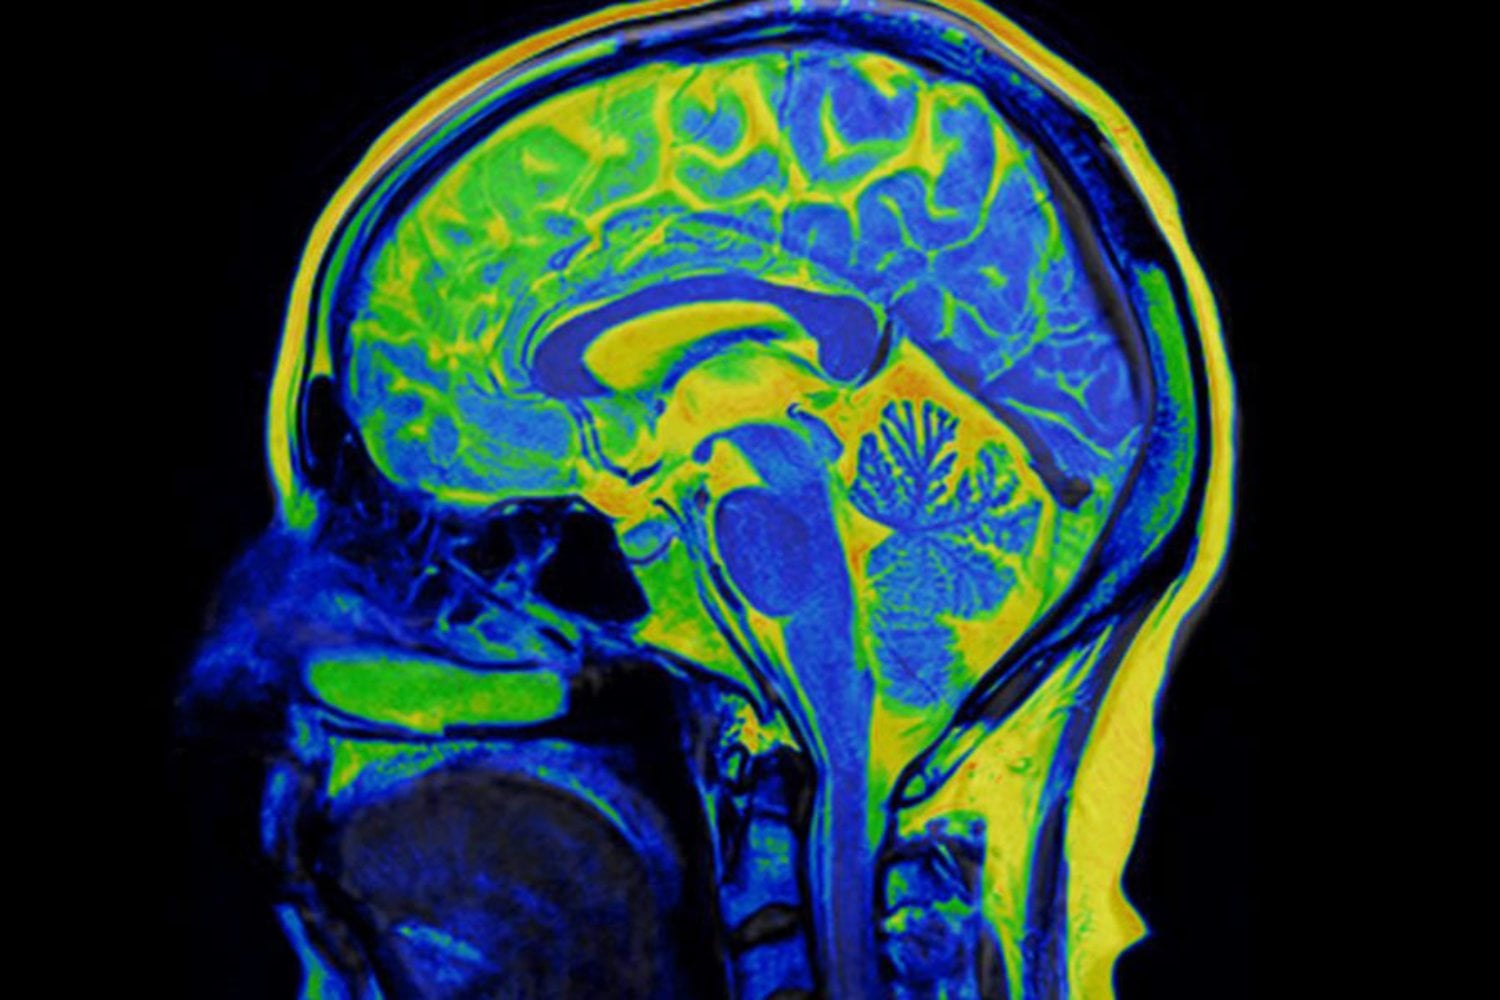

La parte más prometedora del hallazgo es que no se limita a describir un problema, sino que apunta a posibles soluciones. Si KCC2 actúa como un regulador del aprendizaje asociativo, modular su funcionamiento podría ayudar a prevenir o revertir hábitos perjudiciales.

El estudio señala que algunas benzodiacepinas, como el diazepam, mostraron capacidad para influir en la coordinación neuronal relacionada con este proceso. No se trata de una solución inmediata ni de un tratamiento listo para aplicarse, pero sí de una pista valiosa para futuras terapias contra la adicción y otros trastornos del aprendizaje emocional.